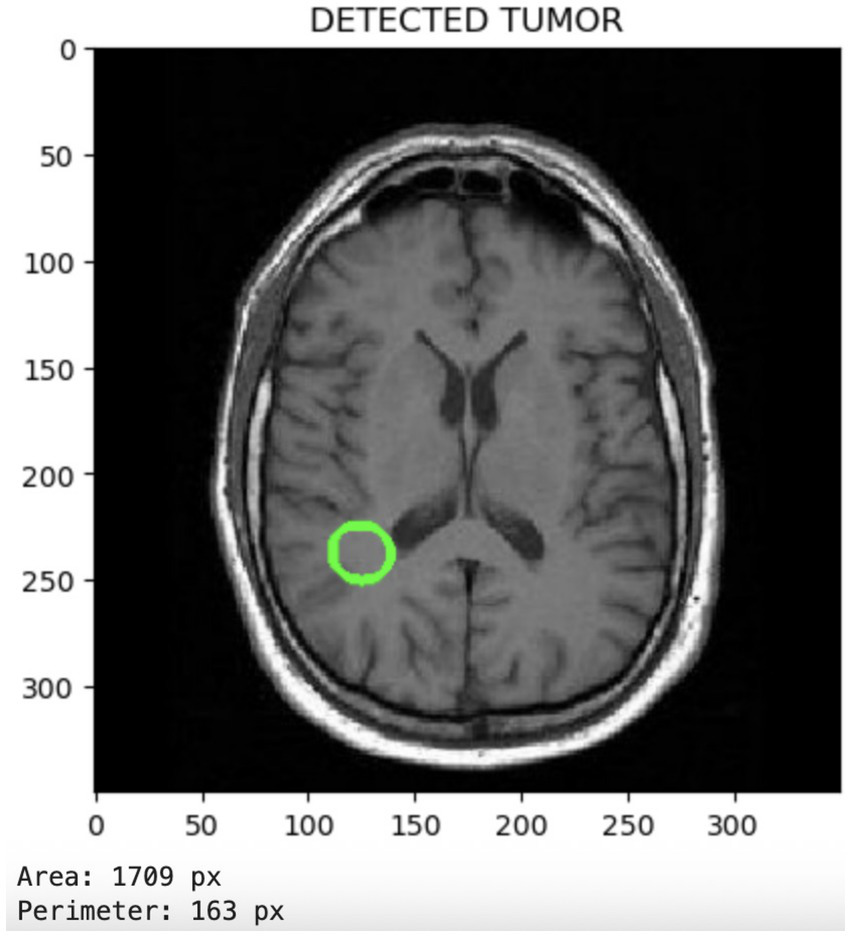

Figure 6 displays the tumor segmentation output, highlighting spatial tumor regions. The trained model not only classifies the presence of tumors but also enables the visualization of the detected tumor region. This segmentation capability adds clinical value by providing spatial context for the tumor’s location and size.

Figure 6

Segmentation output visualizing localized tumor regions, highlighting the model’s spatial discrimination capabilities.